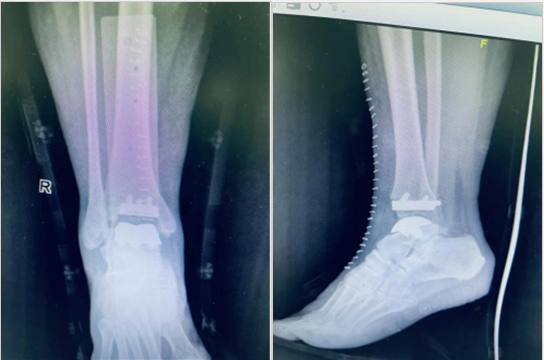

术后复查X线提示右侧人工踝关节置换术后,假体未见松脱、移位及断裂